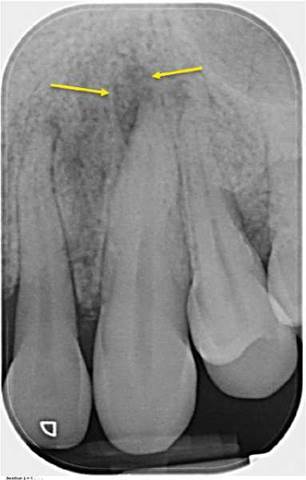

Incisive canal and foramen. The incisive canal is a channel in the bone extending from the floor of the nasal cavity and opening on to the anterior hard palate, in the midline just posterior to the maxillary central incisors. The canal is a conduit for the ascending greater palatine artery and the descending naso-palatine nerve (Figure 6.9). The incisive canal and foramen is represented radiographically as a radiolucency, which may be heart-shaped, oval, round, or a thin wedge. Superimposition of the incisive canal and/or foramen over the apices of the maxillary incisor teeth may mimic a radiolucency associated with AP in conventional radiographs.

Figure 6.9 Incisive foramen. (a) Periapical radiograph of teeth 11, 21 and 22. The incisive foramen/canal (yellow arrows) is represented on the radiograph as an elongated radiolucency between teeth 11 and 21. There is a large periapical radiolucency associated with tooth 22 (red arrow). (b) Sagittal CBCT view demonstrating the incisive canal (between yellow arrows) and the incisive foramen (green arrow). (c) Sagittal CBCT view demonstrating the periapical radiolucency associated with tooth 22 (red arrow) and its relationship with the nasal cavity (pink arrow). (d) Coronal CBCT view demonstrating the relationship of the incisive canal (between yellow arrows) to the nasal cavity (pink arrows) and the periapical radiolucency associated with tooth 22 (red arrow).